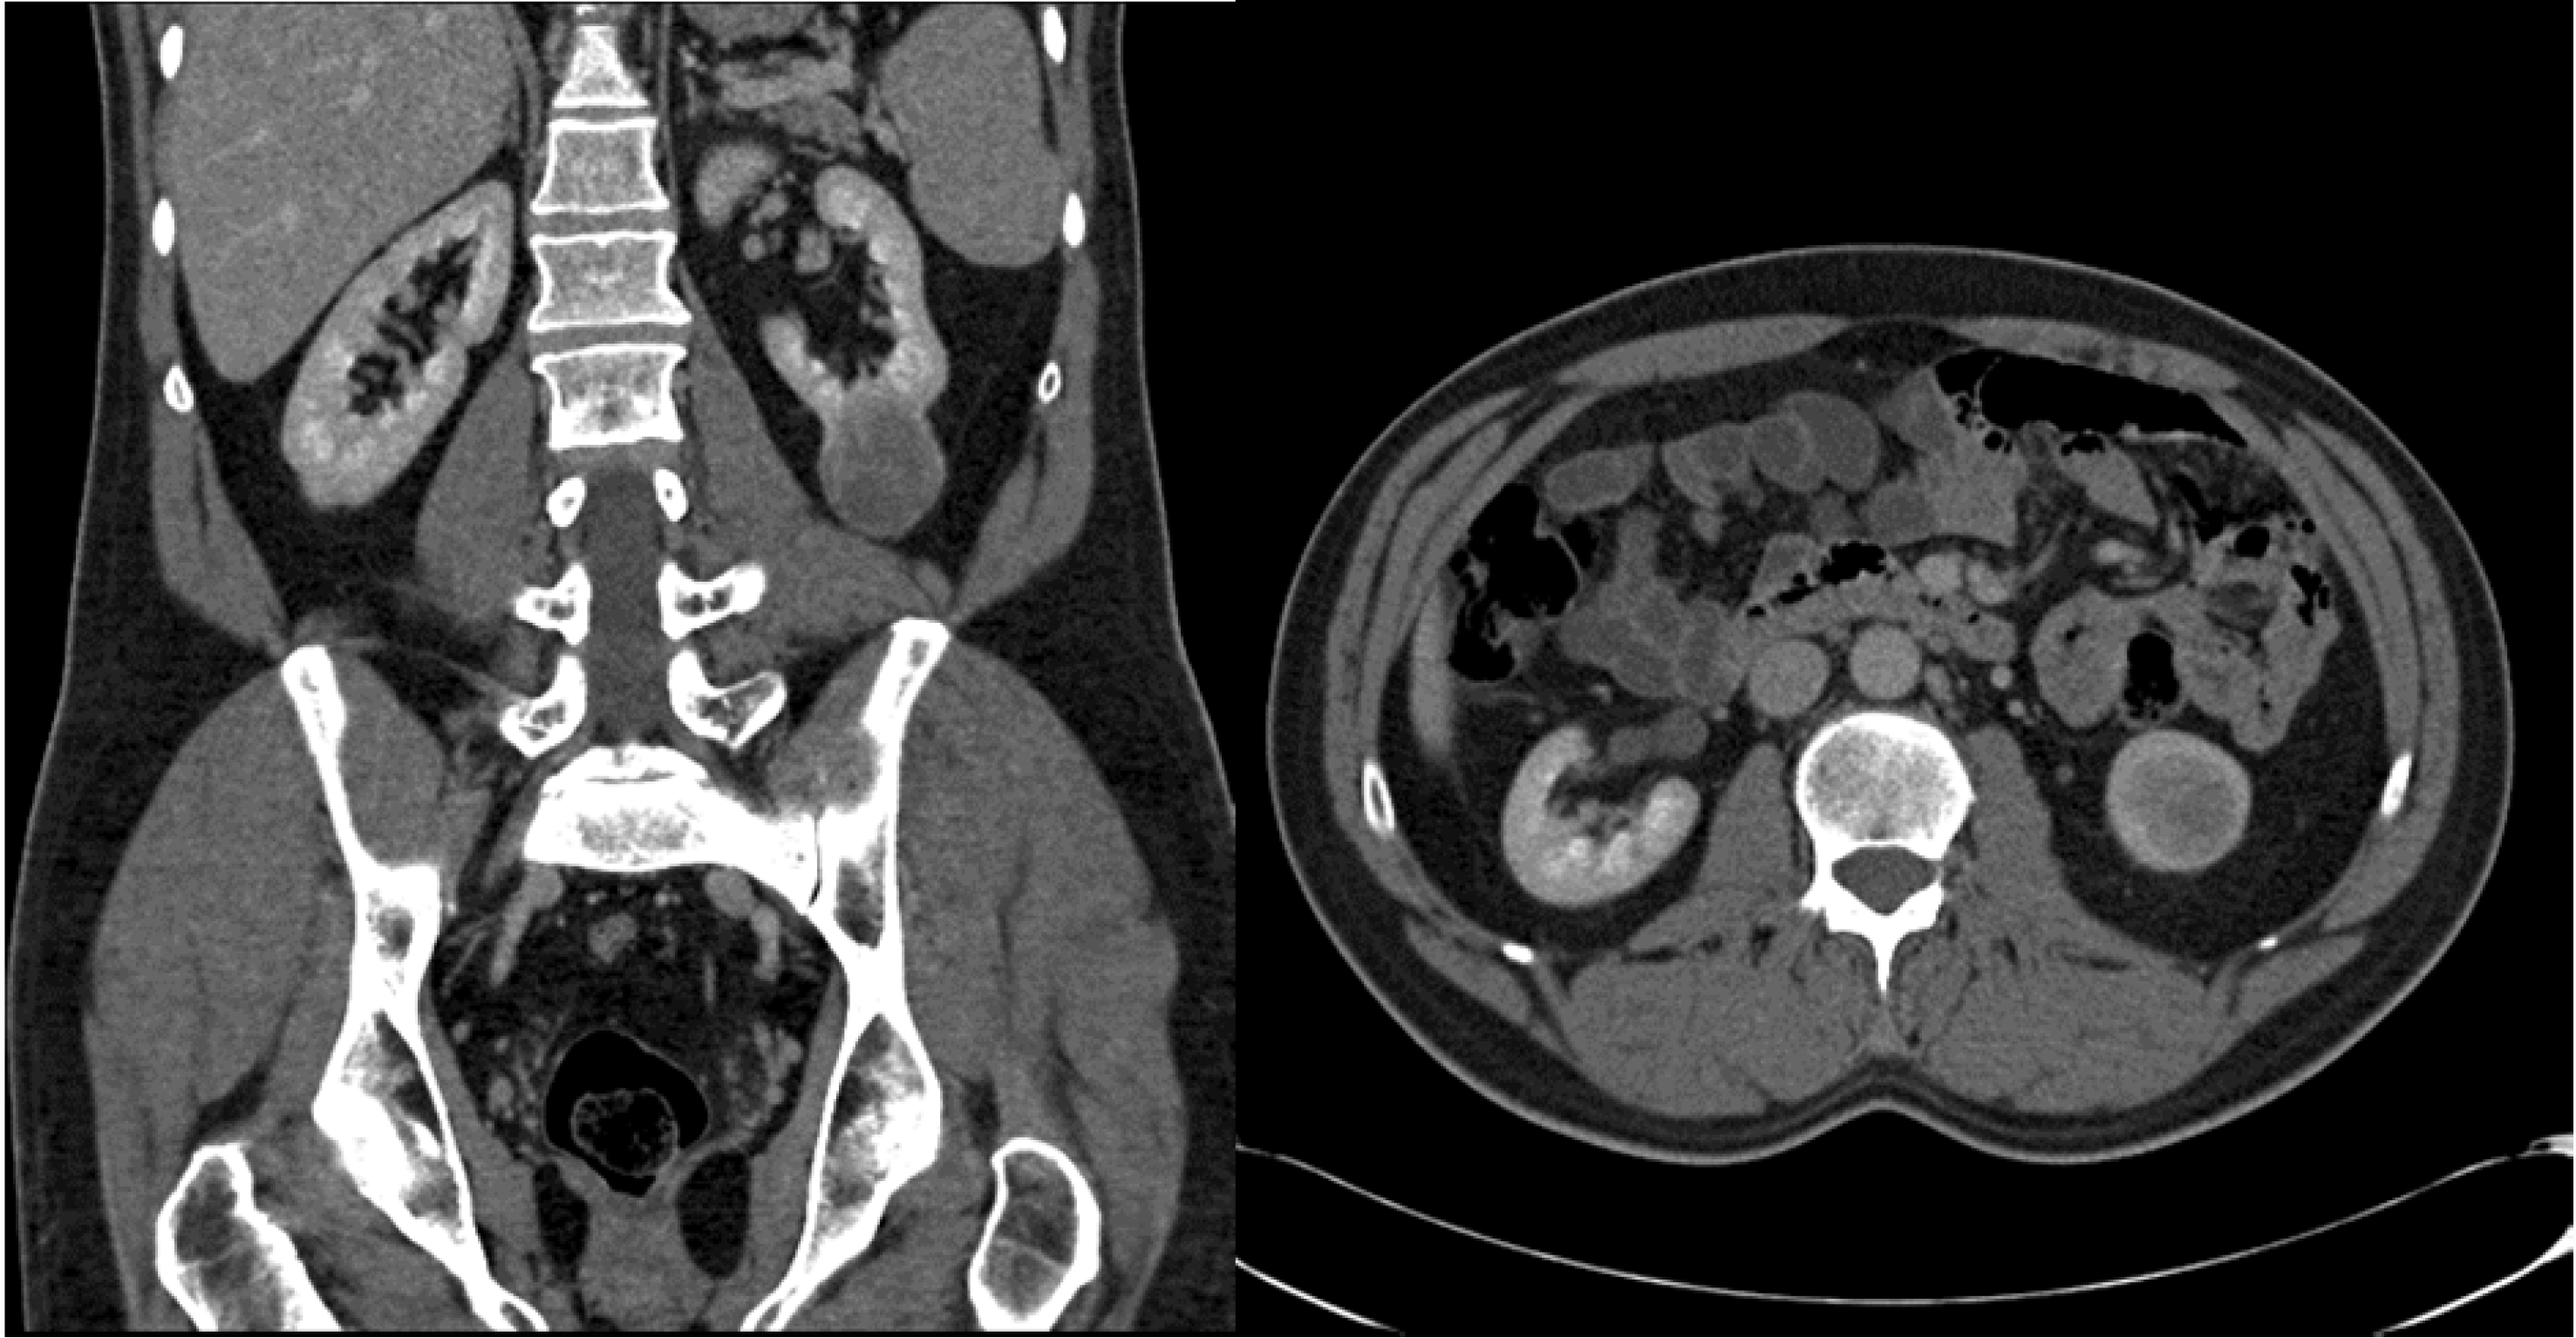

Laparoscopic RADICAL NEPHRECTOMY FOR RENAL CANCER Urologist Kidney Endoscopy Procedure For stones in the kidney, shock wave lithotripsy (swl) is the most common treatment. Like a cystoscope, a ureteroscope has an eyepiece at one end, a rigid. It entails the passage of a small telescope, called a ureteroscope, through the urethra and bladder and up the ureter. An endoscopy is a procedure done to examine structures inside your body up. Kidney Endoscopy Procedure.